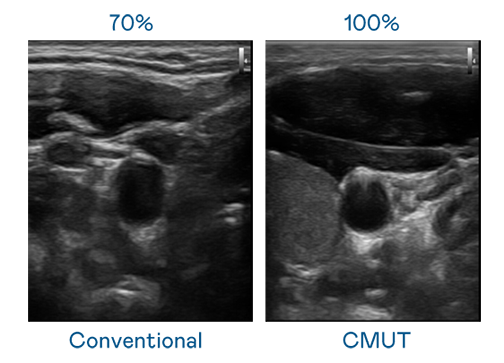

CMUT 技术是一种用电容式微机电元件来产生超音波讯号的技术。与传统 PZT 压电式技术相比,CMUT 频宽增加 30%,更宽频的超音波讯号让影像解析度大幅提升,是实现高影像品质医疗超音波扫描、促进精准医疗发展的关键技术。

超音波影像的解析度高低,首先取决于探头能发出的讯号频宽。5001拉斯维加斯 CMUT 可提供高清晰的超音波讯号,提供高频宽、高灵敏度、影像纹理细节更高的超音波影像,协助医护人员缩短影像判读时间及利用精准的医疗影像进行诊断。